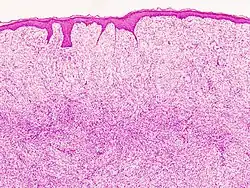

Monotonous, plexiform structure of tumour